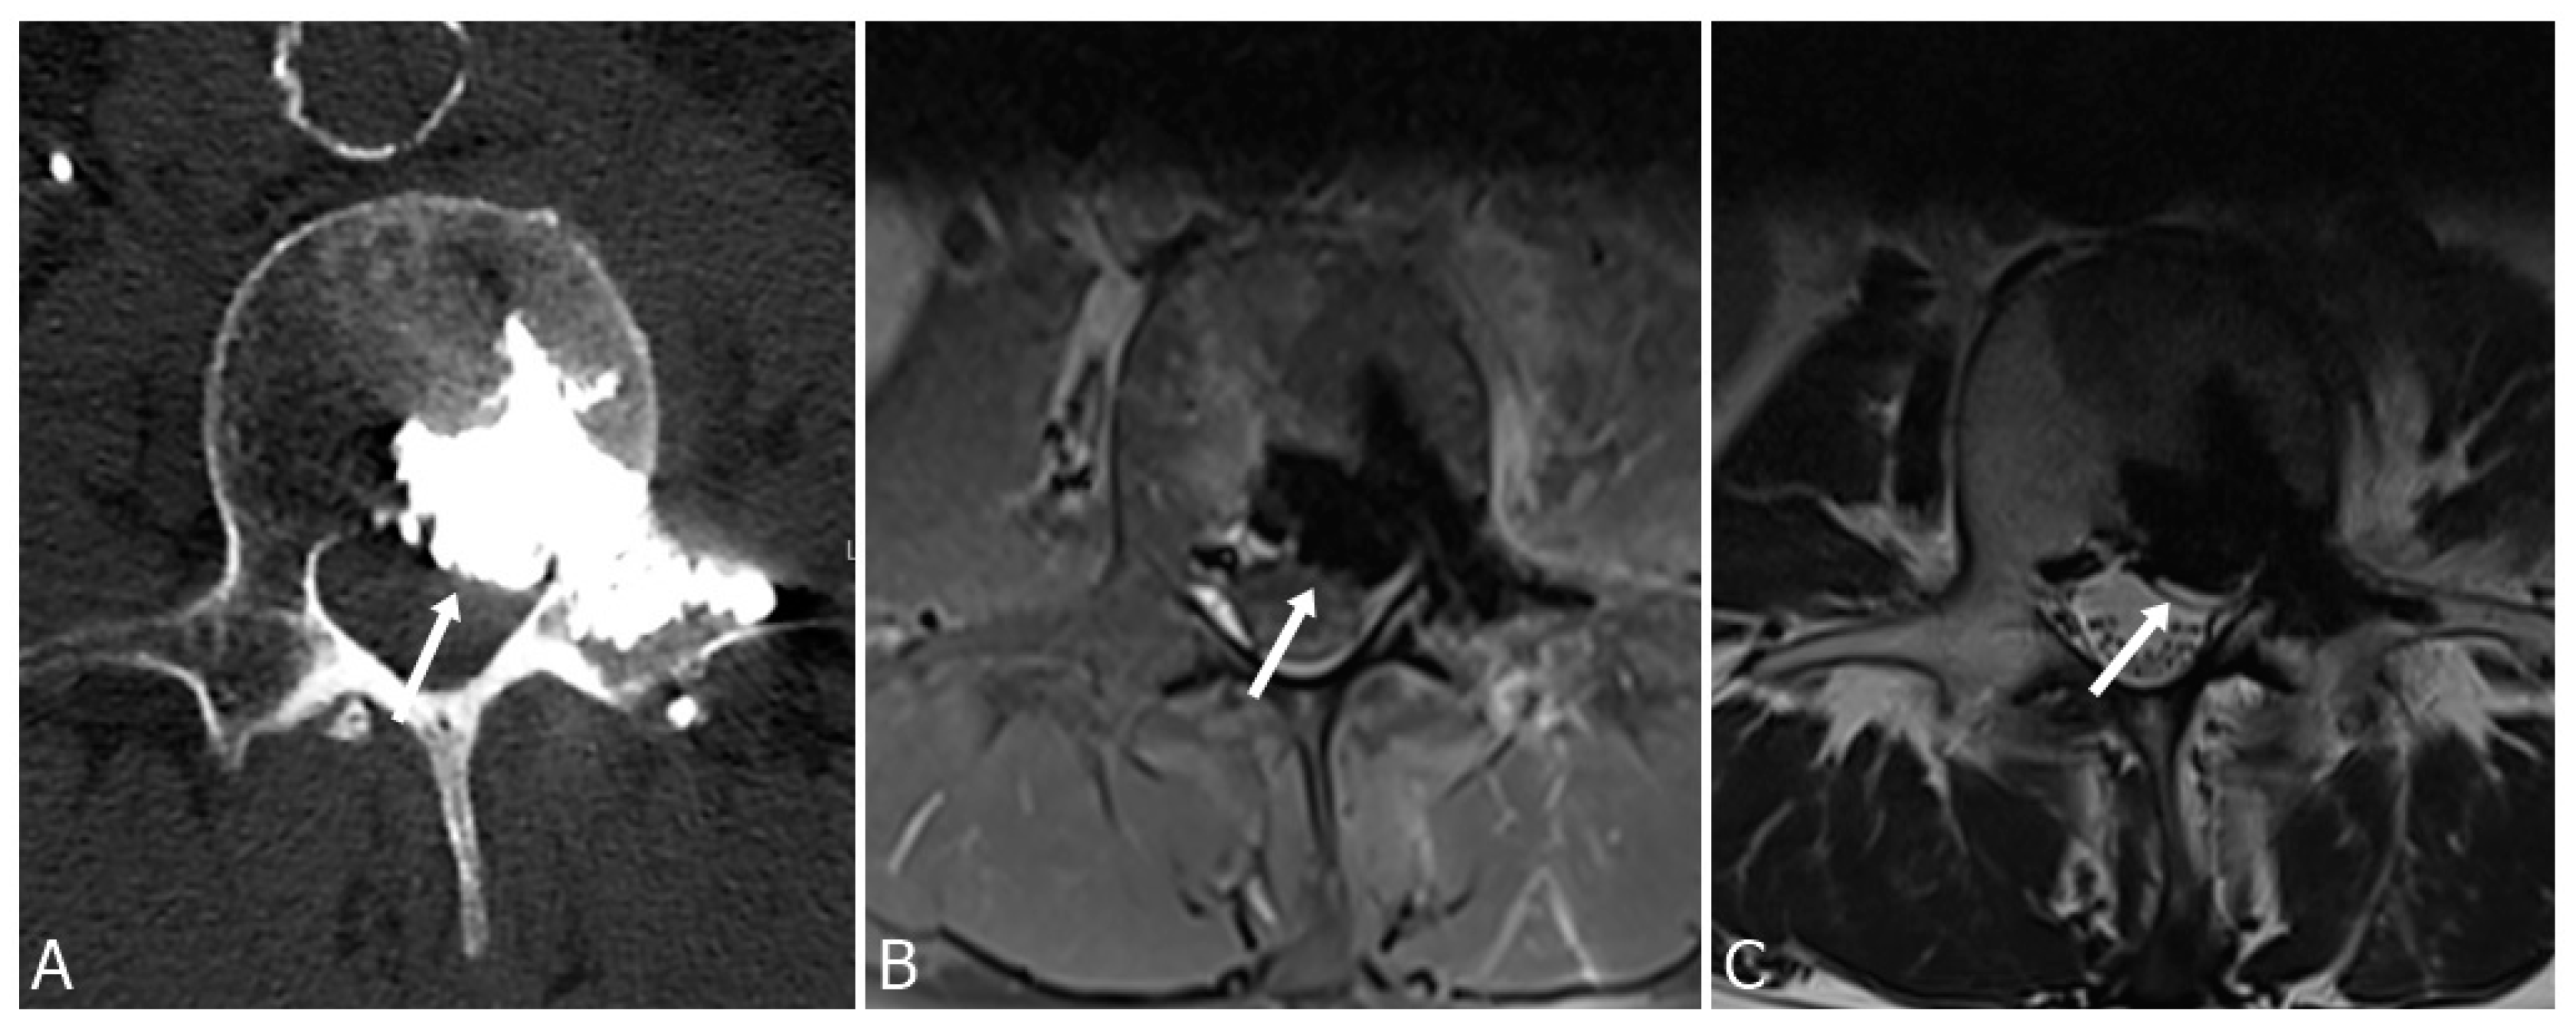

3.1. Epidural and Foraminal Cement Leakage